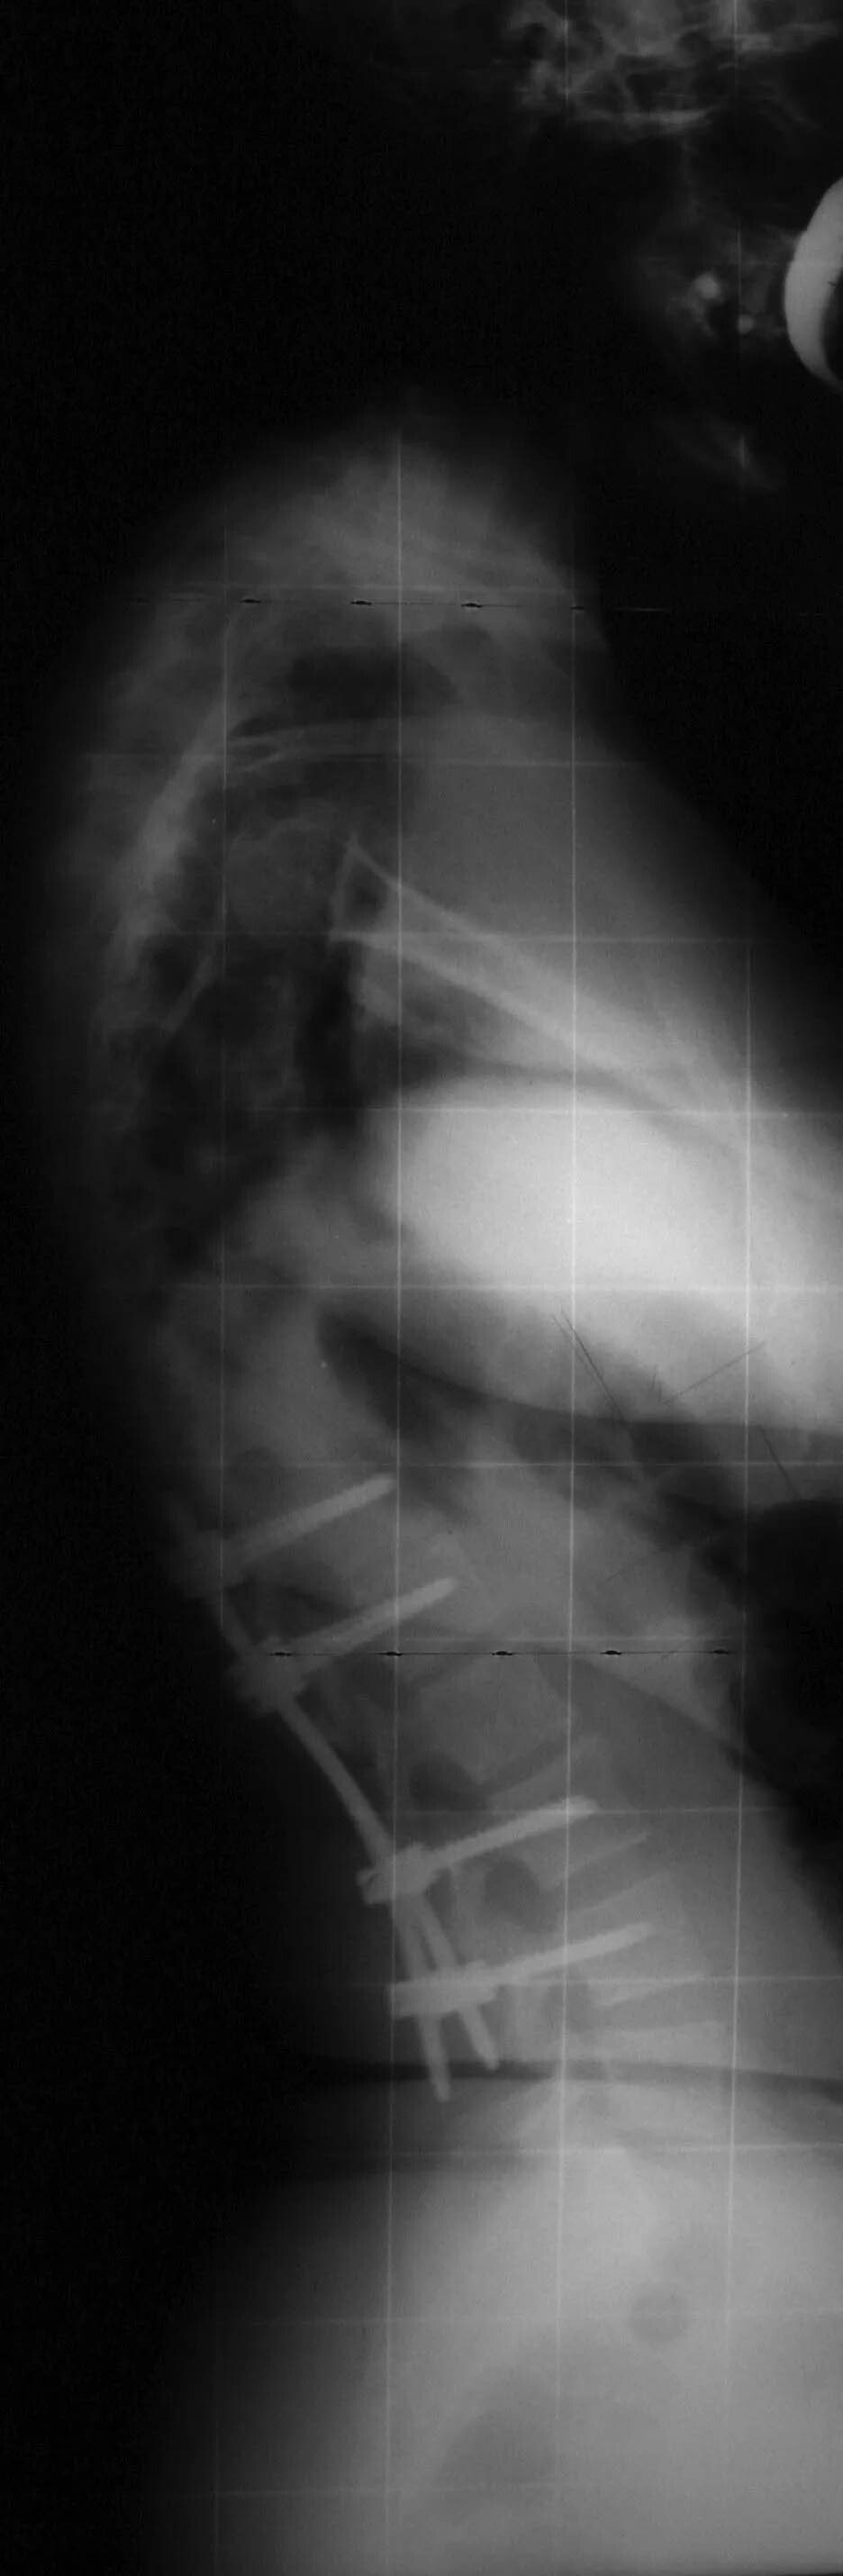

La chirurgia vertebrale rappresenta una delle terapie oncologiche mirate a ridurre o eliminare le masse neoplastiche che provocano il mieloma. La chirurgia vertebrale è una terapia intralesionale che comporta perdite ematiche e necessita di tempi chirurgici molto lunghi. Gli interventi di chirurgia vertebrale, infatti, presuppongono la movimentazione della colonna vertebrale mediante barre, viti e innesti ossei. Richiedi maggiori informazioni riguardo le terapie oncologiche e funzionali destinate alla cura delle fratture vertebrali provocate da mieloma contattando lo studio del dottor Andrea Piazzolla, situato in via Rodolfo Redi 3 a Bari.

Grazie ai nuovi studi e ai progressi della medicina, ad oggi è notevolmente aumentata l’aspettativa di vita dei pazienti che soffrono di fratture vertebrali provocate dal mieloma. Accanto alla chirurgia vertebrale oncologica, infatti, viene sperimentata una terapia funzionale e meno invasiva. La chirurgia vertebrale funzionale, infatti, è in grado di prevenire la perdita delle funzioni neurologiche, ottenendo inoltre una notevole riduzione del dolore e prevenendo l’instabilità vertebrale associata.